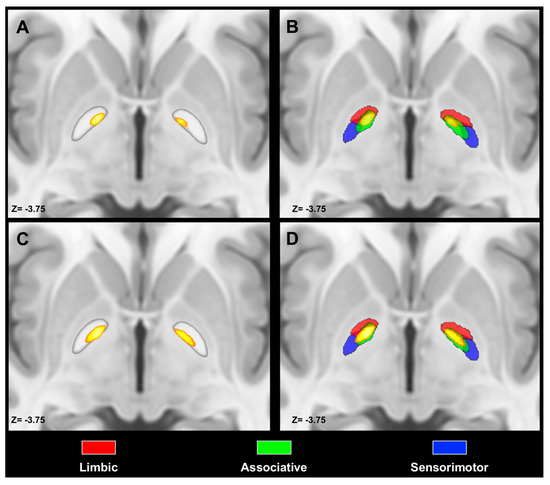

- Bertino, S.; Basile, G.A.; Bramanti, A.; Anastasi, G.P.; Quartarone, A.; Milardi, D.; Cacciola, A. Spatially coherent and topographically organized pathways of the human globus pallidus. Hum. Brain Mapp. 2020. [Google Scholar] [CrossRef]